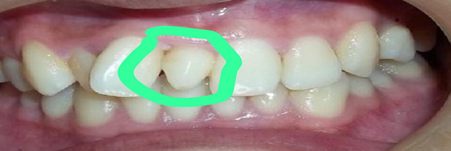

Supernumerary teeth

Additional teeth present in between normal teeth.

વધારાનો દાંત

ઘણીવાર મોઢામાં વધારાનો દાંત હોય છે છે છે અમુક કિસ્સામાં કઢાવો જરૂરી બને છે

Orthodontic Extraction

In some case to create space in arch to movement of teeth

વાંકાચુકા દાંતની સારવાર

ઘણીવાર વાંકાચુકા દાંતની સારવારમાં દાંત માટે જગ્યા કરવા માટે અને દાંતના હલનચલન માટે દાંત કાઢવો પડતો હોય છે